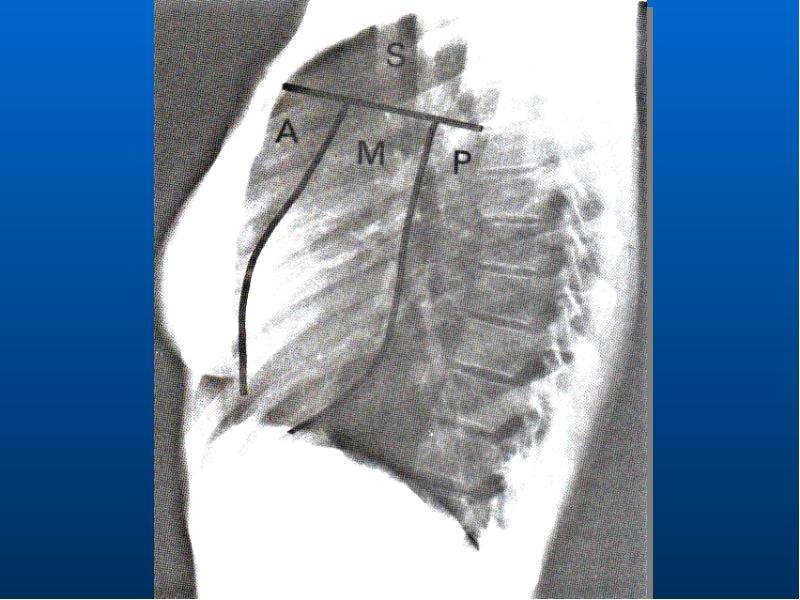

Рентгеновские снимки тератомы средостения: Диагностика и лечение

Раздел: Фотоэссе